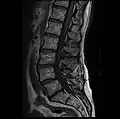

Graphic of lumbar laminectomy and two conditions it can address.

The lamina is a posterior arch of the vertebral bone lying between the spinous process (which juts out in the middle) and the more lateral pedicles and the transverse processes of each vertebra. The pair of laminae, along with the spinous process, make up the posterior wall of the bony spinal canal. Although the literal meaning of laminectomy is 'excision of the lamina', a conventional laminectomy in neurosurgery and orthopedics involves excision of the supraspinous ligament and some or all of the spinous process. Removal of these structures with an open technique requires disconnecting the many muscles of the back attached to them. A laminectomy performed as a minimal spinal surgery procedure is a tissue-preserving surgery that leaves more of the muscle intact and spares the spinal process. Another procedure, called the laminotomy, is the removal of a mid-portion of one lamina and may be done either with a conventional open technique or in a minimalistic fashion with the use of tubular retractors and endoscopes.

The reason for lamina removal is rarely, if ever, because the lamina itself is diseased; rather, it is done to break the continuity of the rigid ring of the spinal canal to allow the soft tissues within the canal to: 1) expand (decompress); 2) change the contour of the vertebral column; or 3) permit access to deeper tissue inside the spinal canal. A laminectomy is also the name of a spinal operation that conventionally includes the removal of one or both lamina, as well as other posterior supporting structures of the vertebral column, including ligaments and additional bone. The actual bone removal may be carried out with a variety of surgical tools, including drills, rongeurs and lasers.